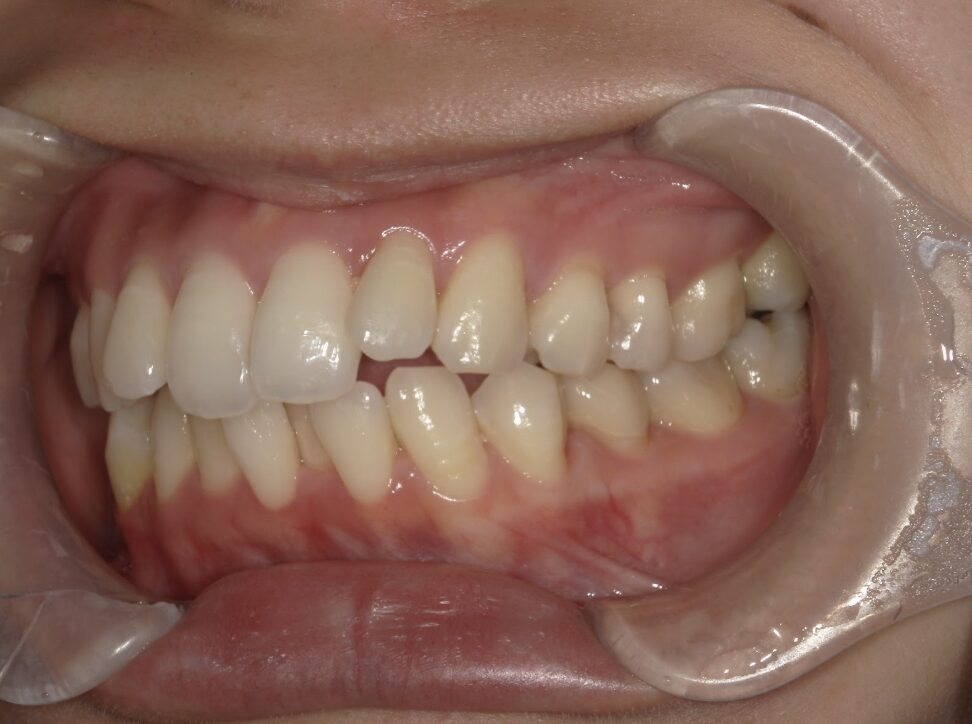

前歯が全く当たっていないを主訴に当院を受診され、開咬・上顎前突・下顎叢生を認めました。

上顎左右4番抜歯を行いIPRを使用してマウスピース型矯正装置(インビザライン)を使用し、改善を行いました。

年齢/性別20代女性

抜歯部位上顎左右4番

治療期間1年9ヶ月